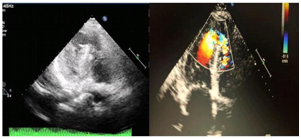

A 68 years old female patient who is a known case of hypertension and dyslipidemia presented to the emergency department with typical ischemic chest pain and electrocardiographic findings of anteroseptal STEMI. Patient received thrombolytic therapy and consequently had coronary angiography and then refered to our hospital, 15days post infarction for further management. Transthoracic echocardiography revealed moderate left ventricular dysfunction, EF 40%, anteroseptal and apical akinesia, small apical aneurysm, large VSR (17'14mm) with dominant left to right shunt and right ventricular systolic pressure of 45mmHg. An informed consent was obtained and the patient prepared for elective cardiac catheterization with intending of transcatheter closure of the VSR. Under local anesthesia and transthoracic echocardiographic guidance , right femoral and internal jugular vascular access was obtained and selective left coronary artery and left ventricle (LAO/Cranial 35/35) angiography was performed (Figure 1).

Figure 1 Transthoracic echocardiographic four chambers view shows the apical ventricular septa! defect with left to right shunt.